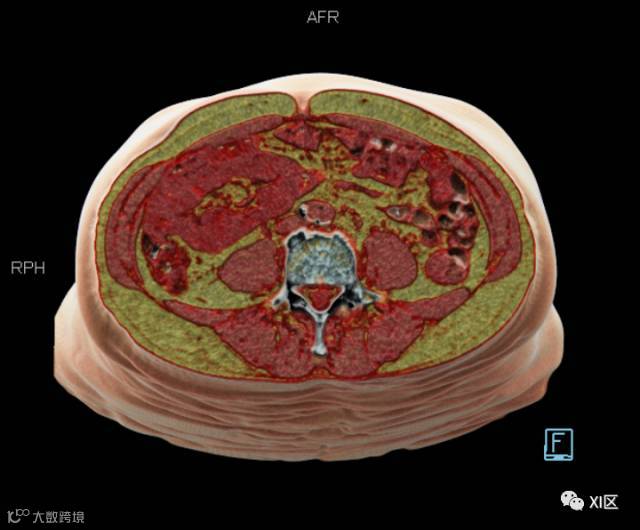

今天我们分享一个利用CT数据和Volume软件精确评估腹部脂肪含量的方法。

再使用自由ROI工具将腹腔内的脂肪勾勒出来,点击开始评估,在右下像格即可获得腹壁和腹腔内脂肪的体积数据。